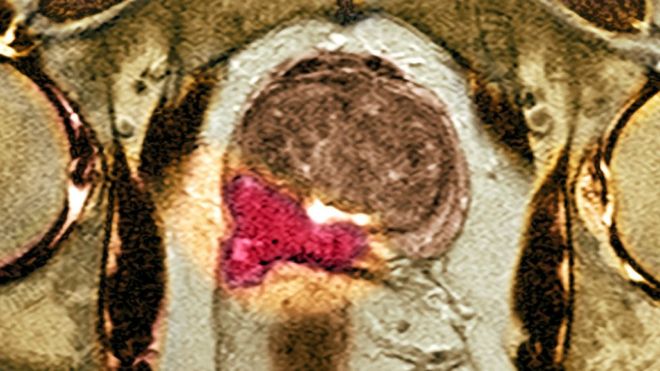

The biggest leap "in decades" in diagnosing prostate cancer has been made using new scanning equipment, say doctors and campaigners. Using advanced MRI nearly doubles the number of aggressive tumors that are caught. And the trial on 576 men, published in the Lancet, showed more than a quarter could be spared invasive biopsies, which can lead to severe side-effects.

Using MP-MRI to triage men might allow 27% of patients avoid a primary biopsy and diagnosis of 5% fewer clinically insignificant cancers. If subsequent TRUS-biopsies were directed by MP-MRI findings, up to 18% more cases of clinically significant cancer might be detected compared with the standard pathway of TRUS-biopsy for all. MP-MRI, used as a triage test before first prostate biopsy, could reduce unnecessary biopsies by a quarter. MP-MRI can also reduce over-diagnosis of clinically insignificant prostate cancer and improve detection of clinically significant cancer.

93% of aggressive cancers were detected by using the MRI scan to guide the biopsy compared with just 48% when the biopsy was done at random.

The trial, at 11 hospitals in the UK, used multi-parametric MRI on men with high PSA levels.

It showed 27% of the men did not need a biopsy at all.